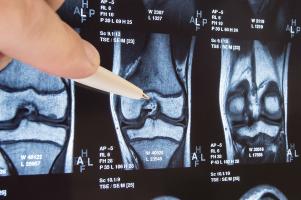

Actualité publiée le 28/01/2019MÉCANOBIOLOGIE : Pourquoi une blessure à l'articulation du genou mène à l'arthrose

Actualité publiée le 16/12/2018